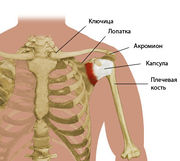

| 05:23, 18 января 2011 | Sholder.jpg (файл) |  |

25 КБ | Admin | 1 | |